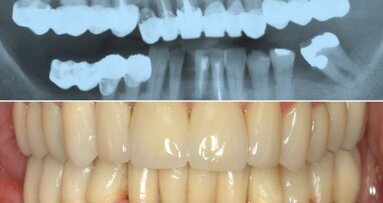

Фиг. 2

80-годишен пациент се яви за преглед на състоянието на зъбите и смяна на протезите (фиг. 1а и б). Наличните му горни и долни цели протези бяха на пет години и нямаха ретенция и стабилност. Периферните граници на двете протези не бяха достатъчно екстензирани и бе налице значително увеличение на вертикалния размер на оклузията (VDO; фиг. 2). Пациентът не бе доволен от външния вид на протезите си, тъй като при тях се наблюдаваше обърната линия на усмивката и прекомерно показване на зъбите на венците (фиг. 3). При приблизително желаното VDO пациентът показа адекватно междучелюстно отстояние и демонстрираше беззъби дъги от клас 2 на Протетичния диагностичен индекс.14 След обстойно обяснение на всички възможности за лечение и техните цели и ограничения пациентът се съгласи на лечение на беззъбите дъги с използване на комбинация от традиционни аналогови и дигитални CAD/CAM техники.

Готовите протези бяха поставени и бе оценена тяхната ефикасност, прилягане, форма и функция (фиг. 14а–в). При оценката с помощта на Pressure Indicator Paste (бял силиконов спрей; Keystone Industries) бяха необходими минимални корекции по вътрешната повърхност. Оклузията, стабилността и задържането бяха оценени и бе установено, че ситуацията е значително подобрена в сравнение с началото (фиг. 15–17). С пациента бяха дискутирани указанията за орална хигиена.